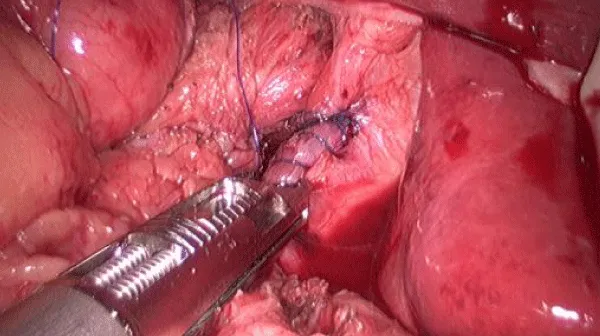

The patient was prepared in a supine position, with the operating surgeon standing on the right side of the patient and the scope holder on the left. ​​A 3-cm horizontal incision was made at the umbilicus, followed by the insertion of a single-port platform and the establishment of pneumoperitoneum.​ To expose the peri-hiatal area, a Veress needle was inserted below the right costal margin, followed by insertion of a latex tube to atraumatically retract the liver (Figure 5). ​Intraoperative exploration confirmed the presence of SIT within the abdominal cavity and type I HH. The diameter of the hiatal defect expanded to approximately 3 cm.​ After standardized dissection, the defect was repaired by firstly approximating the crura with a running 3-0 barbed suture and then reinforcement with a 3-0 nonabsorbable suture applied with an autosuturing device (Figure 6). Nissen fundoplication was completed in a counterclockwise fashion with approximation and reinforcement in the same way (Figure 7). During the wrapping maneuver, a 36F bougie was inserted through the gastric cardia to ensure the appropriate tightness. Finally, no drainage was placed, and the umbilical incision was properly closed. Postoperative recovery was uneventful. The patient took a liquid diet on the first day after surgery and was discharged three days later. At the interview in one month, she was free of GERD-related symptoms or dysphagia, and scored 0 points in GERD-Q. The follow-up CT and gastrogram were consistent with the presentation, indicating complete resolution of GERD (Figures 8,9).

Download Image

Figure 6: Approximation of the crura with an auto-suturing device.